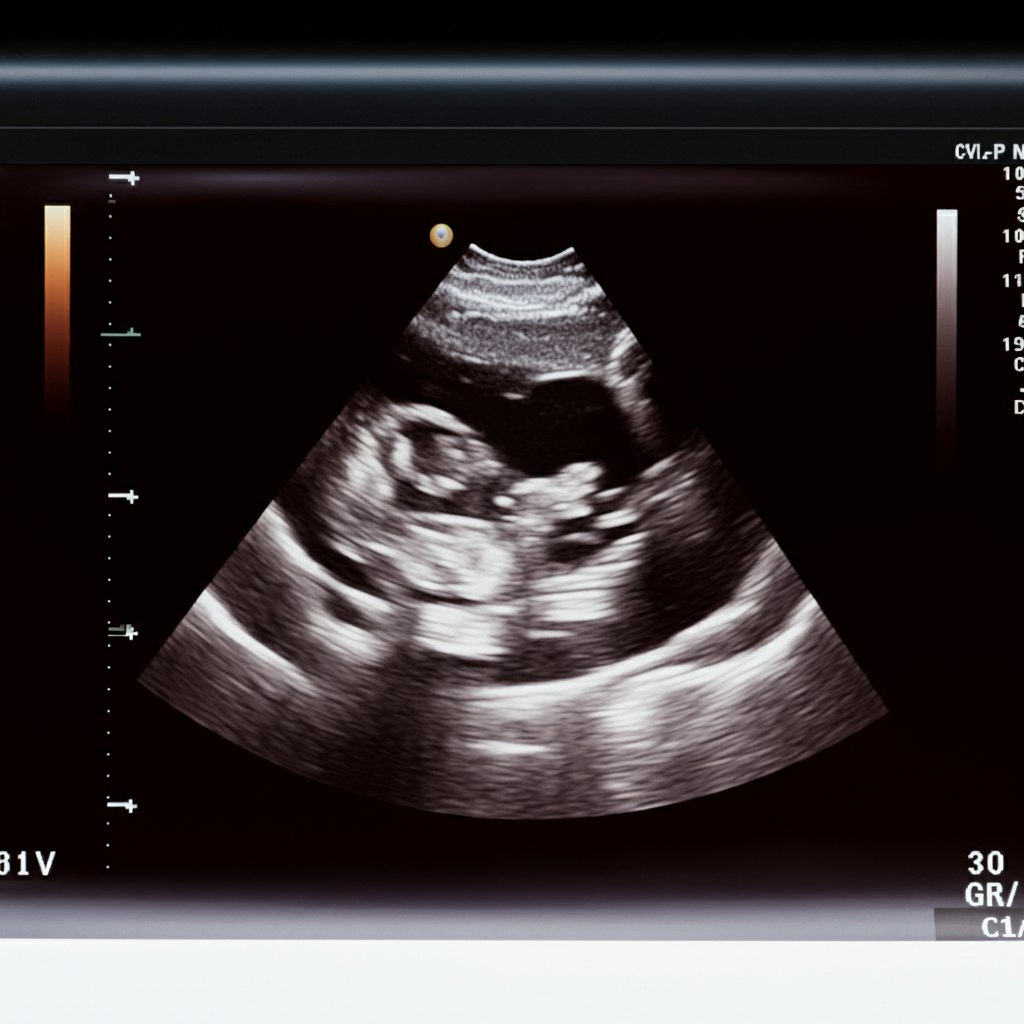

Determined to give the baby a chance, she decided to quit her harmful habits and went through with the plan to have an abortion. However, during her appointment, she had an ultrasound before the procedure. As she saw the baby on the screen with a steady pulse and felt the heartbeat, something changed. The tiny, rhythmic beat made her reconsider. Overcome with emotion, she told the doctor she was sorry and ran out of the room.